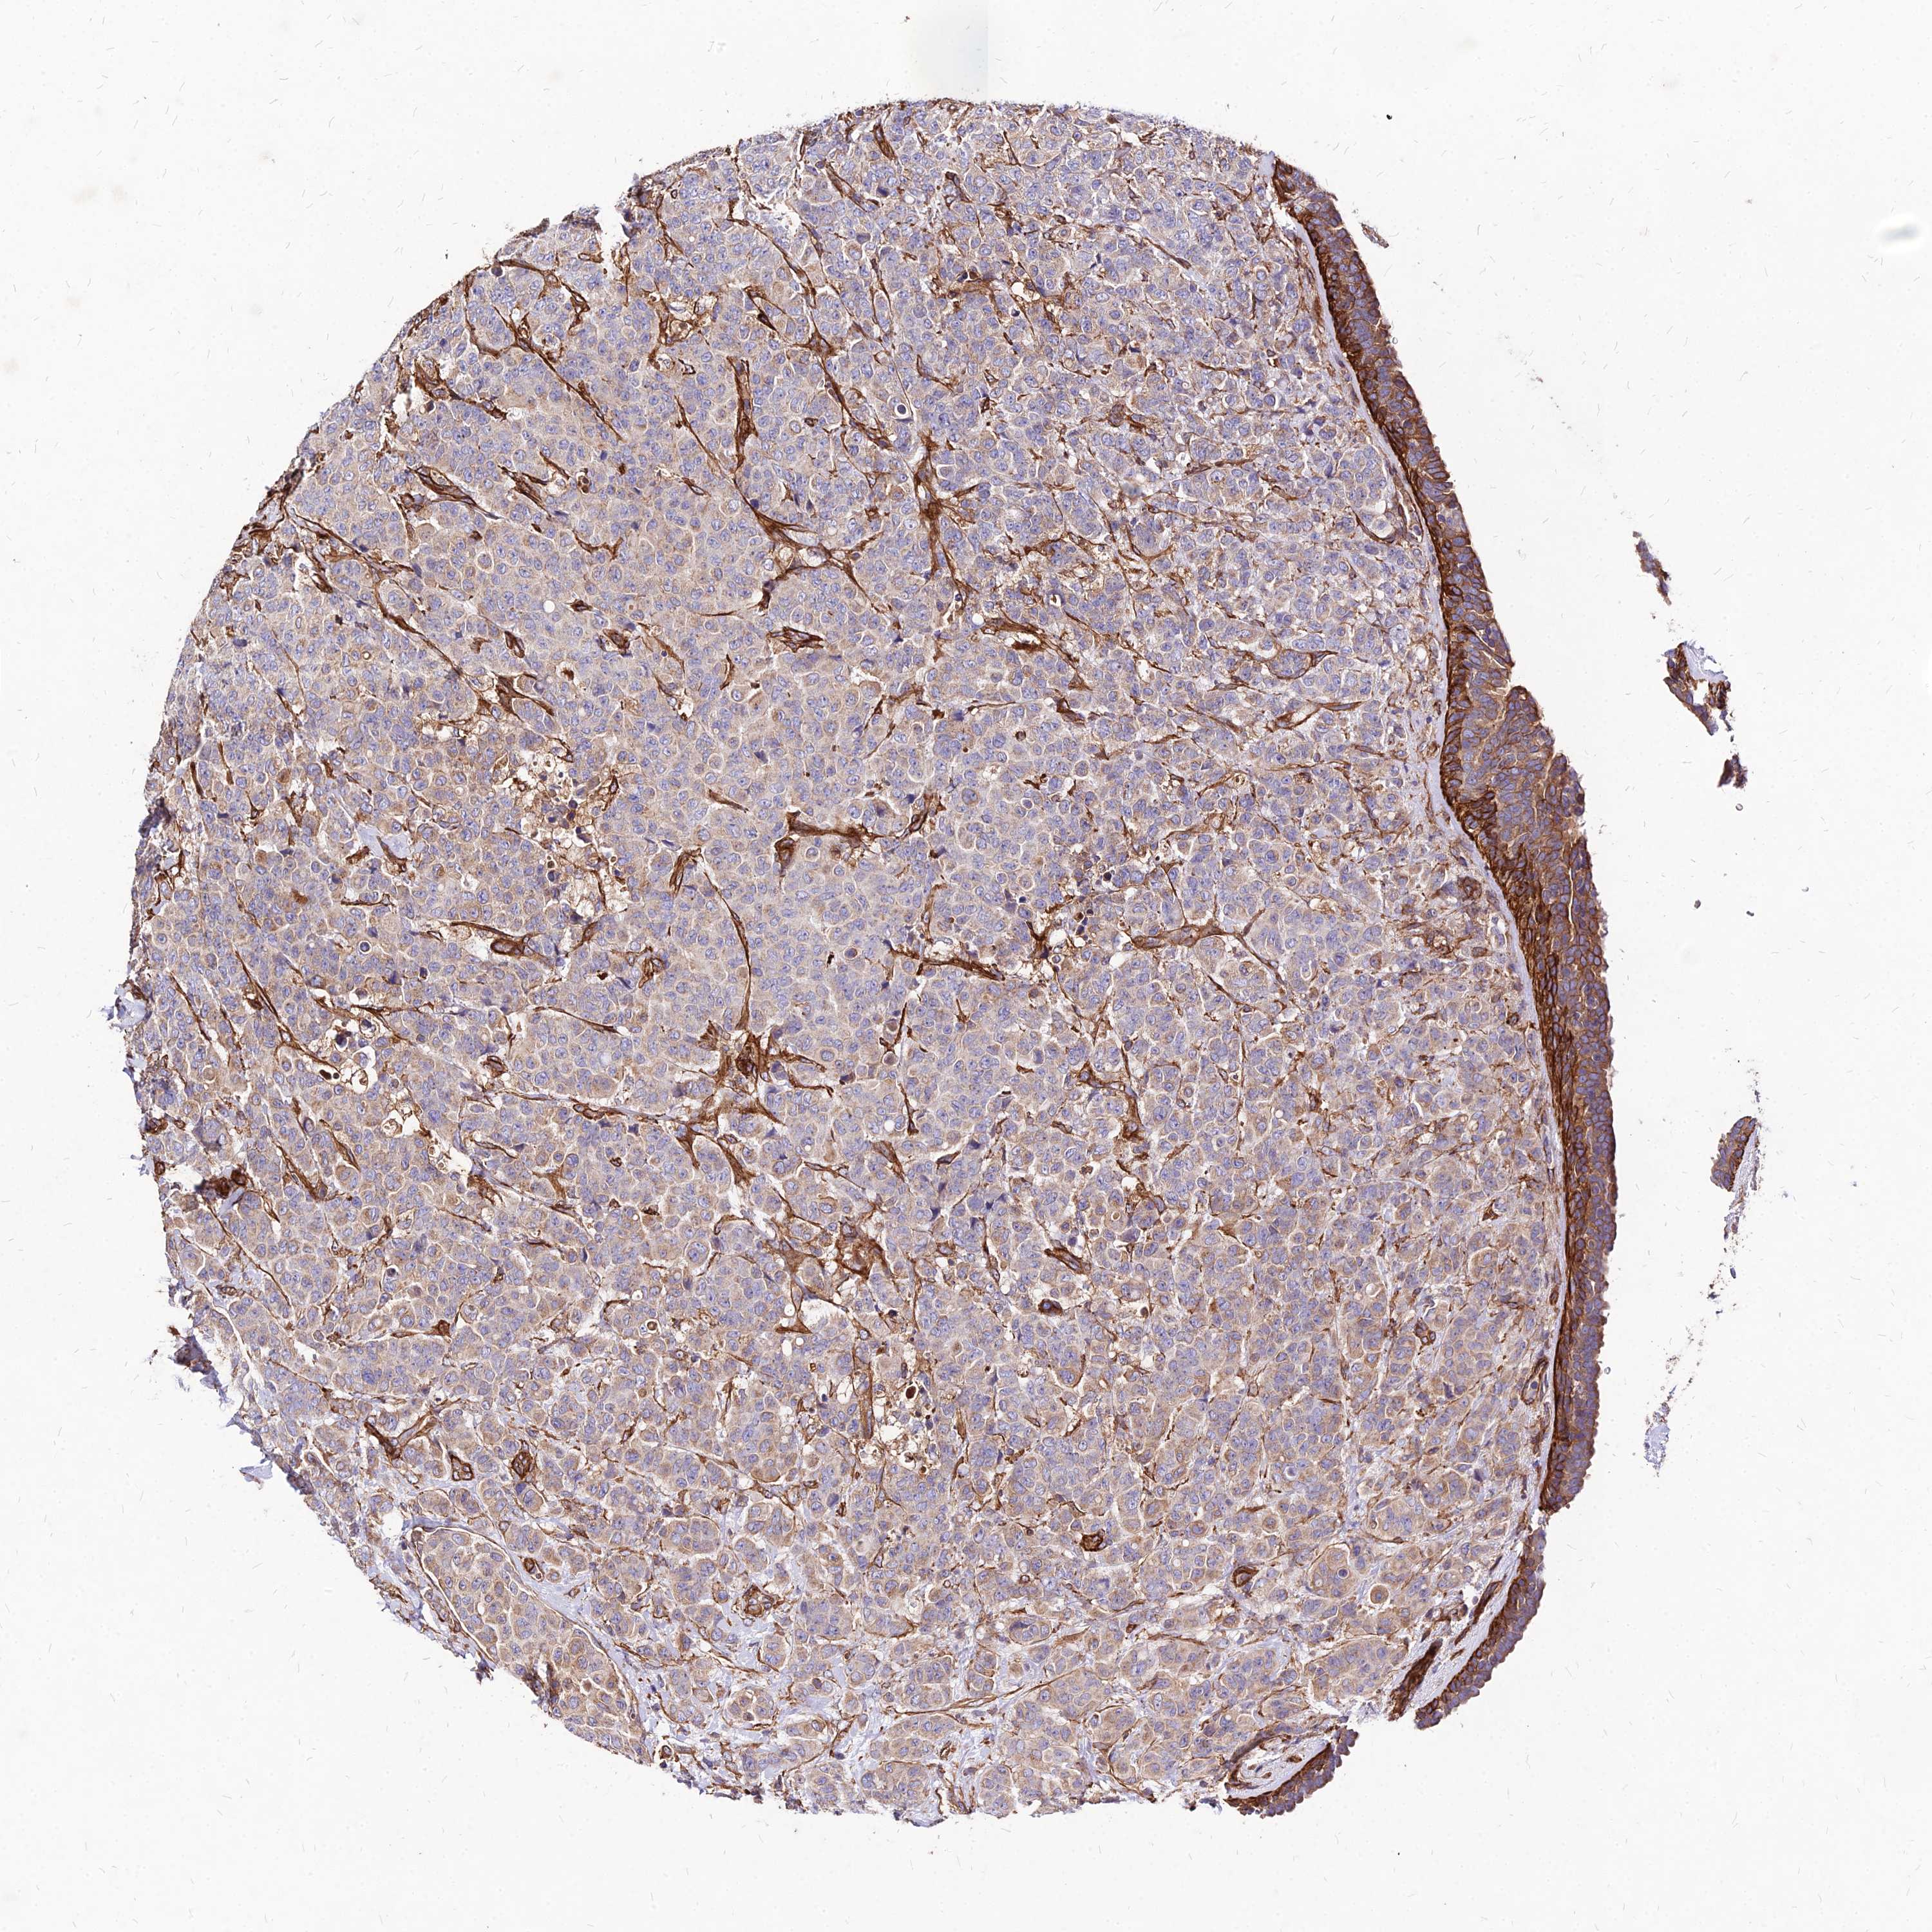

BRCA TCGA BRCA VALIDATION PROTEIN EXPRESSION